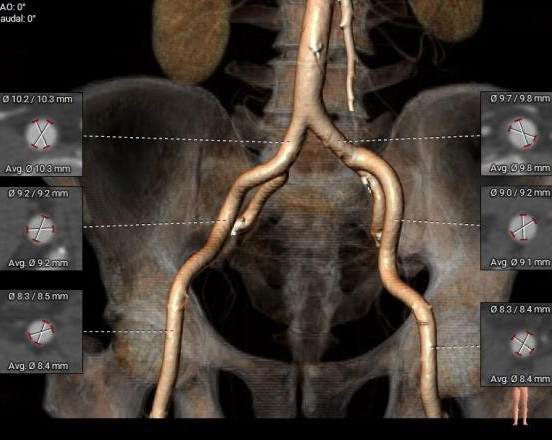

外周入路:

股-髂动脉内径可,走行适宜,腹主动脉少量钙化分布,股动脉无钙化。